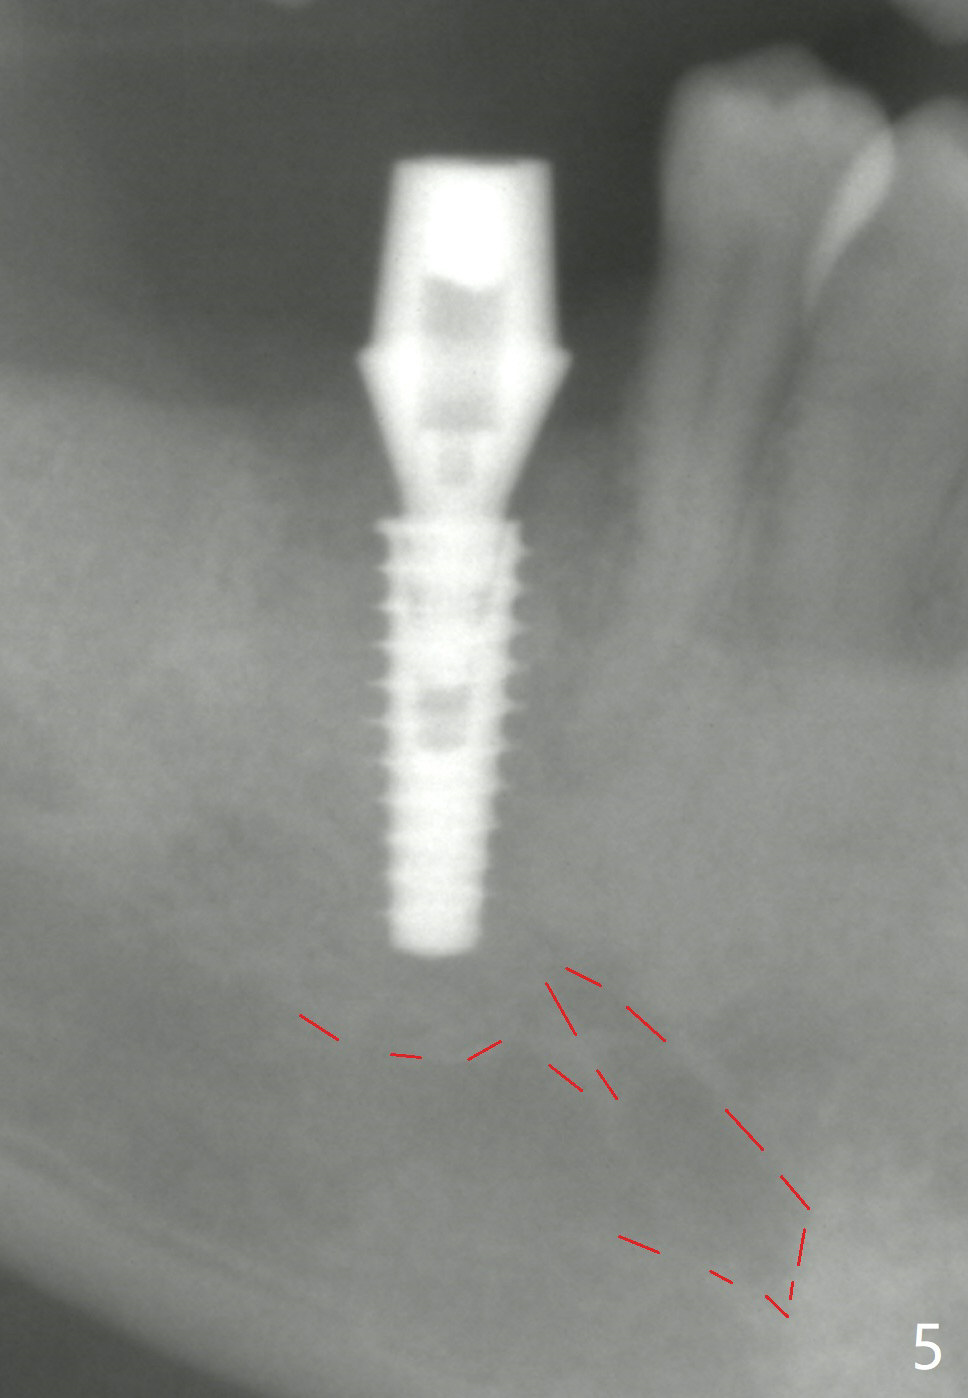

The final implant is placed a little too deep in this case. The problem can be avoided by using Tap with soft tissue depth mark and is solved by using a longer implant (5x13 mm) or having an abutment with longer cuff (5 or 6 mm). Postop there is tooth sensitivity. When the latter disappears, the patient feels the right jaw different. Panoramic X-ray taken 2 months postop shows that the implant has clearance from the Inferior Alveolar Canal (Fig.5 red dashed line).